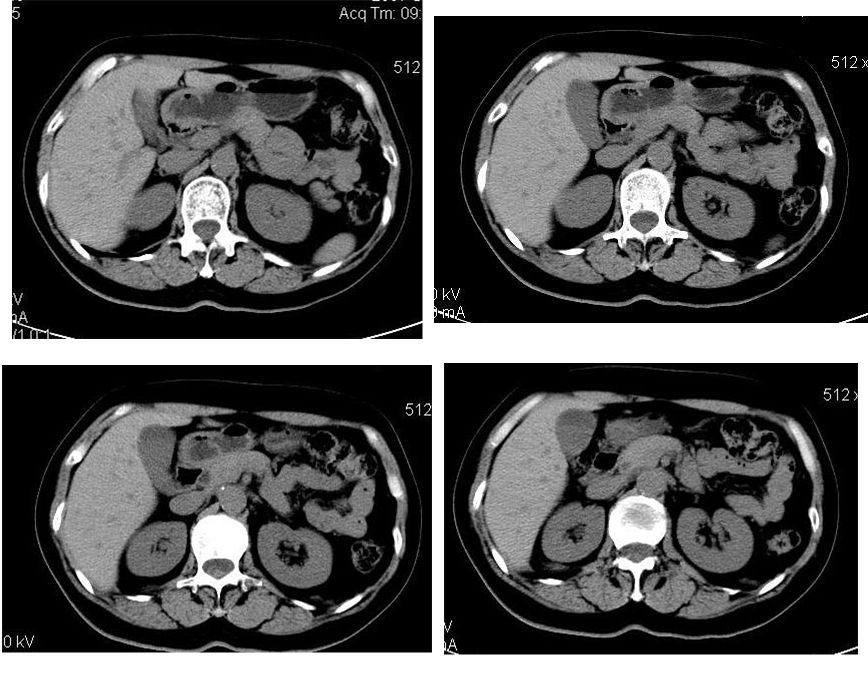

患者,女,65岁,住院准备甲状腺腺瘤用术,术前常规发现肝脏占位,ct增强扫描。

该患者去年9月份在我院ct检查,今年随访,患者家属介绍说上海中山医院做了一个什么检查考虑良性占位,后手术病理是血管平滑肌脂肪瘤。

学习了,这可能是脂肪含量少的血管平滑肌脂肪瘤,因血管丰富所以动脉期密度升高明显,但该患无肝硬化表现,所以,诊断肝癌,依据不足.谢谢上传.对今后工作是一个提醒.

该病例给我们影像医生上了一课,影像上的特征相对性更强。今后工作中吸取教训,避免出现闭门造车的情况,多结合临床的重要性。再次表示感谢